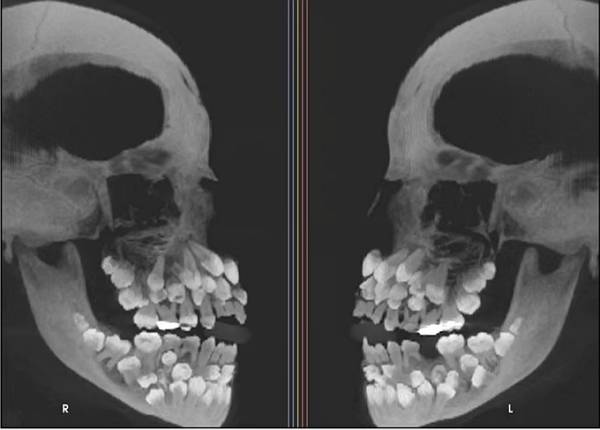

브라질에서 11세 소녀의 입 안에서 치아가 무려 81개가 발견된 희귀 사례가 보고됐다.

A양은 유치 18개, 영구치 32개, 과잉치 31개, 총 81개의 치아를 갖고 있었다.

최근 베트남 매체 VN익스프레스에 따르면 이달 초 브라질에 사는 A양은 위턱에 있는 유치를 발치하기 위해 치과를 찾았다. 그러나 이어진 엑스레이 촬영 결과는 의료진을 충격에 빠뜨렸다. A양은 유치 18개, 영구치 32개, 과잉치 31개, 총 81개의 치아를 갖고 있었다.

이는 희귀 질환인 '다발성 과치증'으로, 정상 치아 개수인 28~32개보다 더 많은 치아를 갖는 질환이다. 과잉치는 1~2개 정도만 발견되는 게 일반적인데 이번처럼 30개가 넘는 과잉치가 확인된 것은 전 세계적으로도 드물다.

CT 검사 결과 다발성 과치증과 흔히 동반되는 구개열, 쇄골두개 이형성증, 가드너 증후군 같은 질환은 나타나지 않았다. 이후 진행된 염색체 검사에서 9번 염색체 일부가 거꾸로 뒤집히는 현상이 발견되긴 했지만, A양의 증상과 직접적인 연관성이 있는 지는 불분명하다.

소녀는 치료에도 어려움을 겪고 있다. 과잉치를 발치할 때는 턱 뼈 손상을 야기할 수 있기에 신중히 접근해야 하고, 잇몸 밖으로 드러나지 않은 치아도 있어 진짜 치아와 과잉치를 구분하기도 쉽지 않다. 현재 A양의 치료를 위해 구강안면외과, 교정과, 치주과, 보철과의 전문의들이 협력을 계획 중이다.